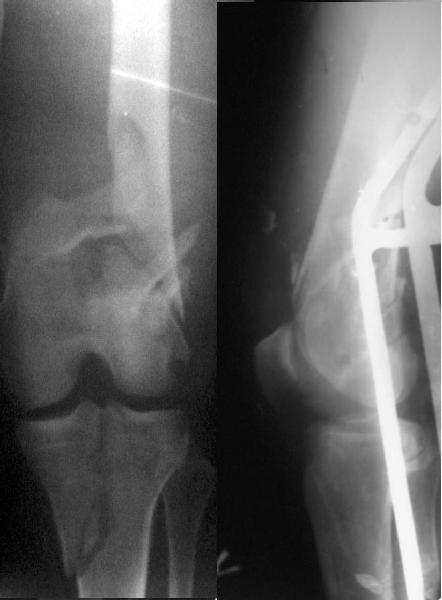

Отправитель: Zsolt Balogh 31 Октябрь 2004, 12:13

This is what we have done... As generally true for LISS look at the bone not the hardware.

There are two more srews above. The one not completely in got damaged head.

Zsolt